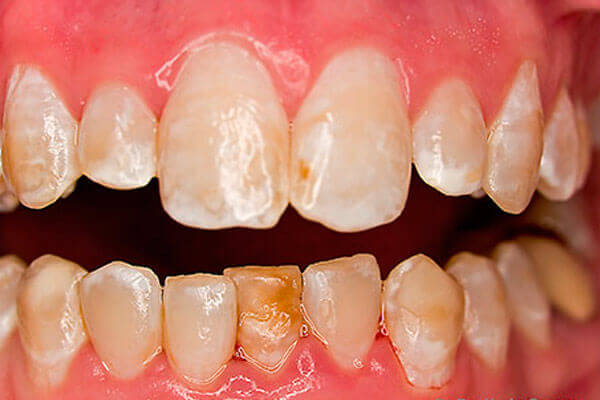

В норме зубная эмаль блестящая, гладкая. При флюорозе эмаль на пораженных участках тускнеет и белеет, становится словно мел. В дальнейшем эти участки могут накапливать пигмент и окрашиваться в желтый, коричневый цвет.

Эрозивная и деструктивная формы

При эрозивной форме на фоне измененной, окрашенной эмали формируются ее дефекты, именуемые эрозиями. Дефекты могут быть абсолютно различной формы. Во время осмотра стоматолог определяет стирание эмали и даже дентина.

Для деструктивной формы свойственно изменение формы зубной коронки в результате разрушения твердых тканей. Зубы, попросту говоря, крошатся и ломаются.